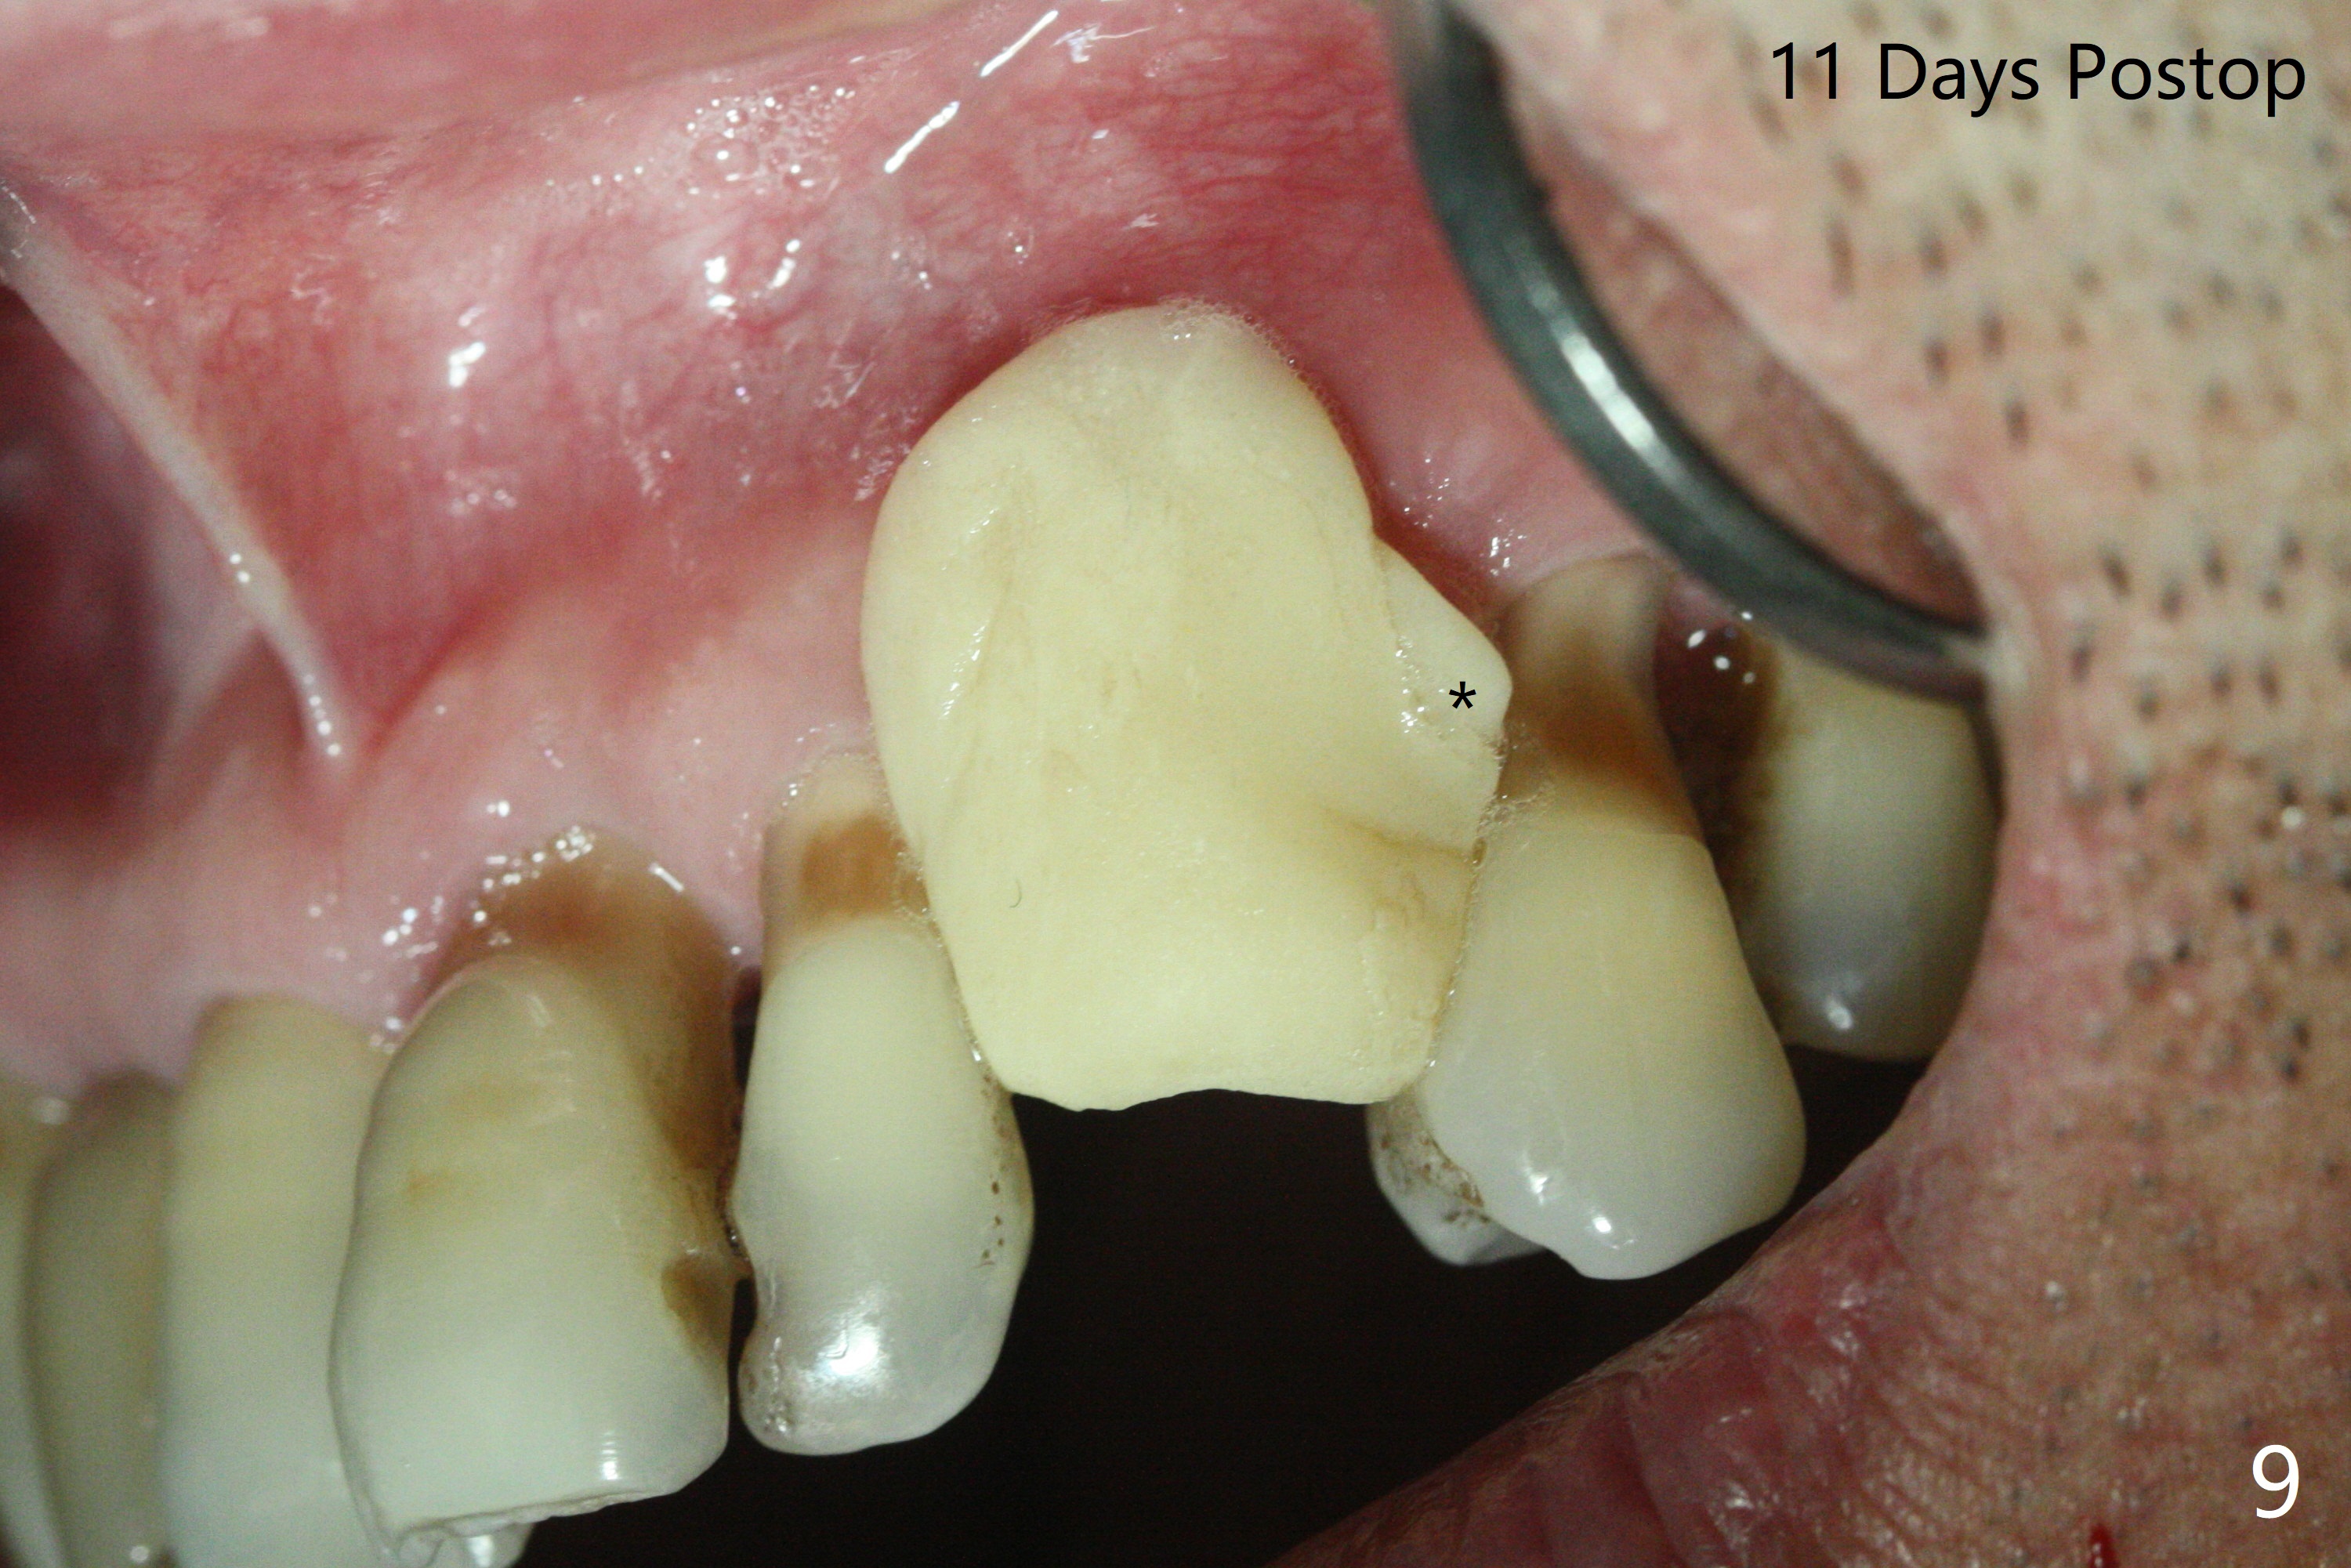

A 62-year-old man with generalized chronic periodontitis returns with chief complaint of loose tooth at #11 (Fig.1). Although a buccal fistula (Fig.1 <) is closer to #12 than to #11, percussion is more severe at #11 than 12. The buccal plate of #11 is missing, but it is possible to place a narrow immediate implant because of the wide alveolus (Fig.2). Since the gingiva is ~ 10 mm long, a mill abutment is to be used (Fig.3,5). In fact the fistula communicates with #11 extraction socket. After debridement, osteotomy is initiated (Fig.4) for a 3.8x10 mm implant ~ 35 Ncm, followed by seating a 4.5x2 mm mill abutment (Fig.5). Abundant sticky bone is placed in the remaining socket (for buccal plate reconstruction) and against the root surface of the neighboring teeth (Fig. 6 * (#10,12)). Finally 2 pieces of PRF membranes are utilized to facilitate repair of the buccal soft tissue defect (Fig.7 *). The root prominence of the canine seems to be maintained by the bone graft (Fig.8 C). Acrylic dressing holding the PRF membranes in place remains in situ with the healthy gingiva buccal (Fig.9) and palatal (Fig.10) 11 days postop. Note the acrylic locking into the undercuts of the neighboring teeth (*). 经过一段摸索发现离心每分钟1500转5分钟后,抽取上清液,接着再离心10分钟剩余上清液就形成血小板块,压制后便是血小板膜,后者似乎有助于软组织愈合,而上清液用来制备骨块,帮助硬组织生长。利用这个原则讨论以下病例治疗。The gingival margin gains ~ 5 mm 6 weeks postop when the acrylic dressing is removed (Fig.11,12 (<: previous one), as compared to Fig.7,8). 治疗结束时尖牙牙龈缘高于第一双尖牙(图七,八),六个星期后,尖牙牙龈缘却低于双尖牙(图十一,十二(箭头:原始牙龈缘))。术后2.5,4.5月基台周围牙龈似乎能与钛合金附着,防止细菌进入深部植体(图十三,十四)。临时牙冠脱落多次,可能与mill abutment太光滑有关,所以颊侧,舌侧磨成平面(图十四)。取模时好像不必取出基台清洗(仿佛没有炎症),原位用树脂延长基台。术后5个月CT显示颊侧骨板再生(图十六-十八)。取模时并没有用树脂加长基台;粘固时,牙冠颜色理想,但是照片中并不是如此(图十九,二十),颊侧骨板没有塌陷。术后11个月基台颊侧骨板没有萎缩(图二十一:B);3d图像:骨壁完全形成(图十六对比:部分形成)。密度也增高(图二十二:B),与术后五个月比较(图十七)。术后十一个月,粘固后五个月角化龈存在(图二十三),牙冠颈部有金属颜色透出,是因为二段式基台太粗了(最细4.5毫米),可以请实验室在牙冠内部涂opaque material而减轻。